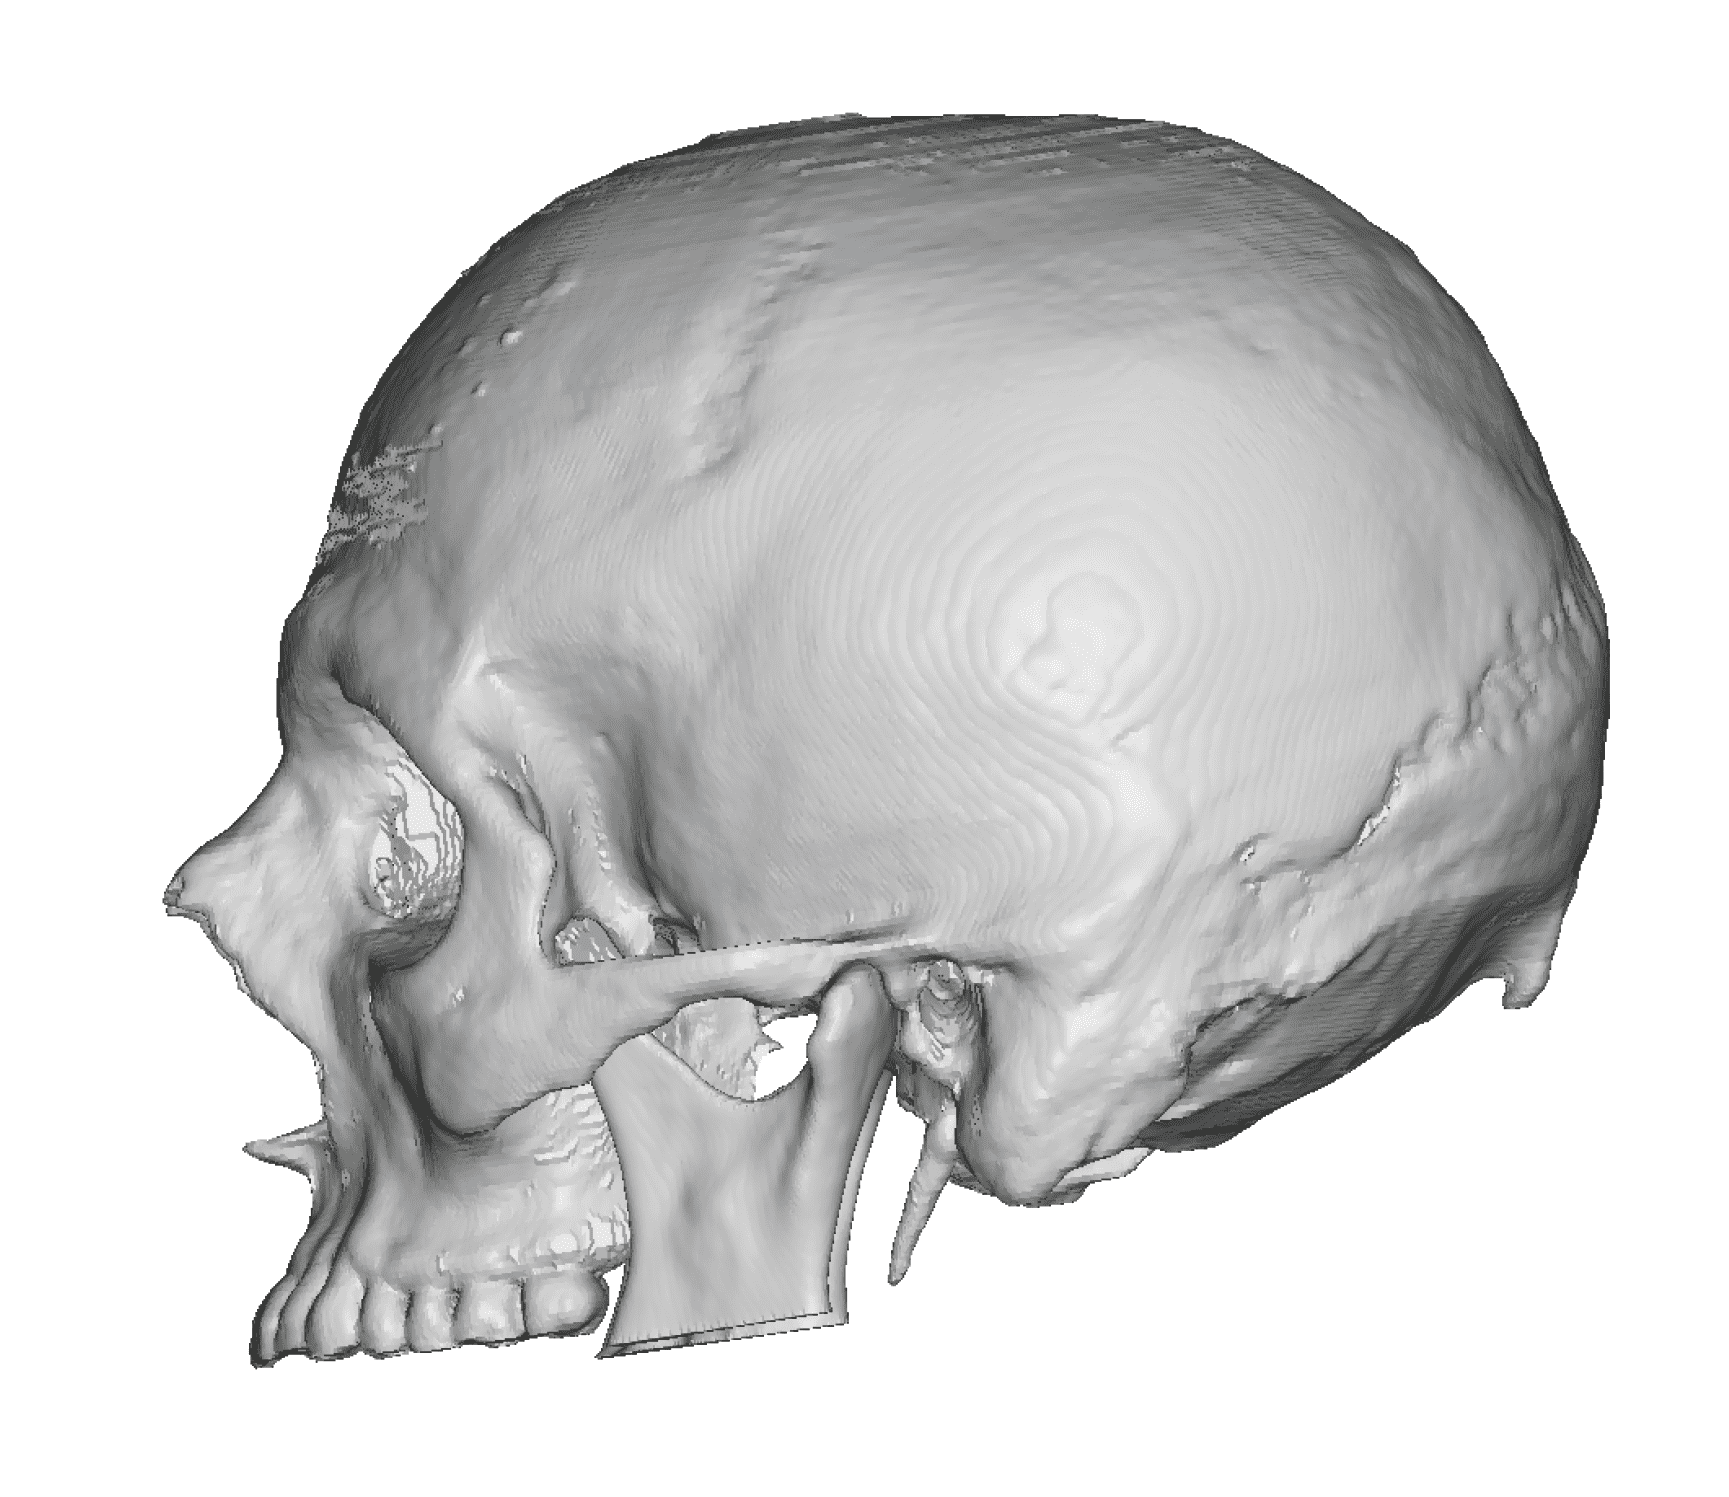

Severe narrowing skull deformity from prior sagittal craniosynostosis repair as an adult.

Complete replacement of entire skull by a custom implant with temporal fat injections.